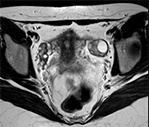

МРТ яичников Исследование выполнено в фазу цикла, при наполненном мочевом пузыре. Матка в положении anteversio, anteflexio, правильной формы, нормальных размеров, контуры ее четкие, ровные, структура гомогенная. Яичники обычно расположены, с четкими контурами, нормальных размеров, с хорошо развитым фолликулярным аппаратом. Мочевой пузырь расправлен, стенки его не изменены, содержимое однородное. Клетчаточные пространства таза дифференцированы. Крупные сосуды таза не изменены. Увеличенных лимфоузлов, костной деструкции на исследованном уровне не определяется. ЗАКЛЮЧЕНИЕ по снимку МРТ яичников: Патологических изменений яичников не выявлено.